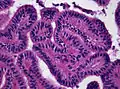

Micrograph of a choroid plexus papilloma. H&E stain.

Micrograph of a choroid plexus papilloma. H&E stain. Plexuspapillom Detail

Plexuspapillom Detail Plexuspapillom Overview